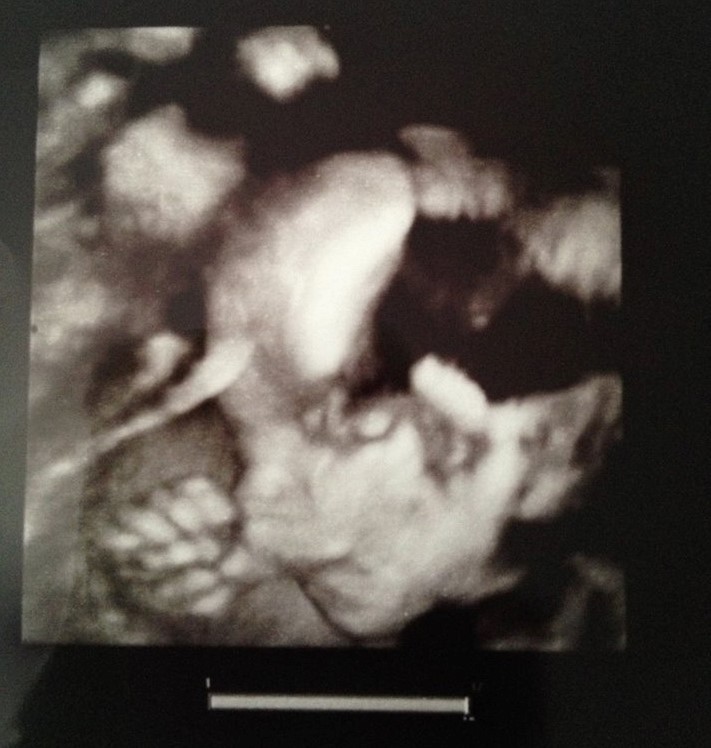

Z niewielkim poslizgiem, ale jednak :D moj kochany synek luzak:D Peace :D

• usg2.jpg

usg2.jpg

105,6 KB · Wyświetleń: 149